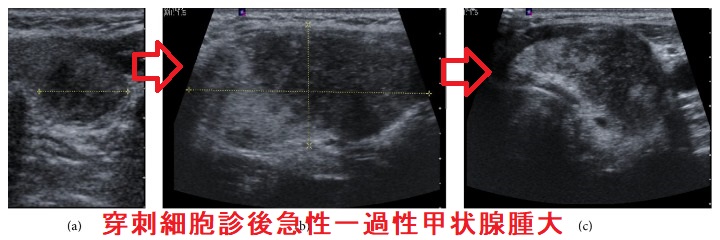

下の写真は、(a)穿刺前→(b)穿刺後→(c)回復後の変化です(Case Rep Endocrinol. 2016;2016:2915816.)

甲状腺穿刺細胞診自体はうまく行ったのに直後(1-3分後)から数時間後、急激な穿刺部の痛みと甲状腺腫脹(急性反応、急性一過性甲状腺腫大)がおこる。穿刺刺激により血管透過性物質(サブスタンスP やニューロキニンA などのタキキニン)が放出された可能性。穿刺時出血と鑑別要。超音波エコー画像所見は甲状腺腫大、前頚筋腫大と線状の無エコー帯/樹枝状低エコー/Hypoechoic cracks(ひび割れ)(ドプラーで血流乏しく、エラストグラフィーで軟らかい)を。治療は、念のため入院し局所冷却、ステロイド点滴静注(メチルプレドニゾロン125-250mg程度)。

甲状腺穿刺細胞診自体は、うまく行ったのに、直後(1-3分後)から数時間後(5-6時間後)、急激な穿刺部の痛みと甲状腺びまん性腫脹を来す症例があります。穿刺細胞診後急性反応、あるいは急性一過性甲状腺腫大と呼ばれます(そのままやな・・)。順天堂大学の報告では、0.13%の確率で起きるとされます(J Ultrasound Med. 2016 Mar;35(3):599-604.)。

穿刺細胞診後急性一過性甲状腺腫大は、穿刺部を中心に超音波(エコー)で、

- 甲状腺びまん性腫大(両側性だが片側性、左右非対称の事も)、あるいは甲状腺外側を取り囲むような前頚筋腫大

- 線状の無エコー帯/樹枝状低エコー/Hypoechoic cracks(ひび割れ)

(ドプラーで血流乏しく、エラストグラフィーで軟らかい):おそらく穿刺刺激により、何らかの血管透過性物質が放出されたためと推察されます。 -

甲状腺推定重量は、穿刺30 分以上すると2倍以上で、甲状腺内部の血管は拡張、